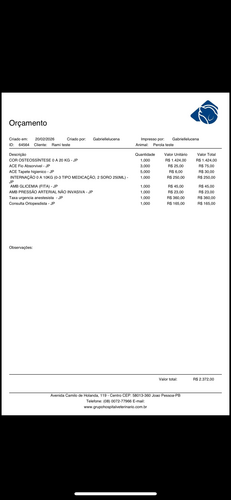

Por ser muito filhote , o Jujuba precisa de atendimento em clínica particular, com todo o cuidado e acompanhamento especializado. O valor da cirurgia é de R$ 2.372,00, e sua contribuição, por menor que seja, fará toda a diferença na recuperação dele.